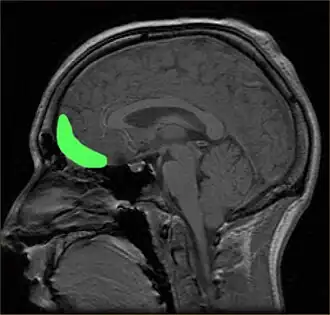

![]() Расположение орбитофронтальной коры на снимке МРТ | |

Орбитофронтальная кора (ОФК) — участок префронтальной коры в лобных долях головного мозга, принимающий участие в принятии решений. У человекообразных обезьян ОФК представлена совокупностью полей Бродмана под номерами 11, 12 и 13; у людей эта кора представлена полями 10, 11 и 47[1].

Орбитофронтальная кора анатомически синонимична вентромедиальной префронтальной коре. ОФК выделяется отдельно, поскольку содержит определенные нейронные связи, а также выполняет строго определенные функции. Принято считать, что ОФК является частью префронтальной коры, которая получает сигналы от магноклеточных нейронов, медиальных ядер таламуса, и принимает участие в представлении эмоций и поощрений во время принятия решений[2]. Название ОФК получила из-за своего расположения в области лобных долей, находящейся выше глазниц (орбит).